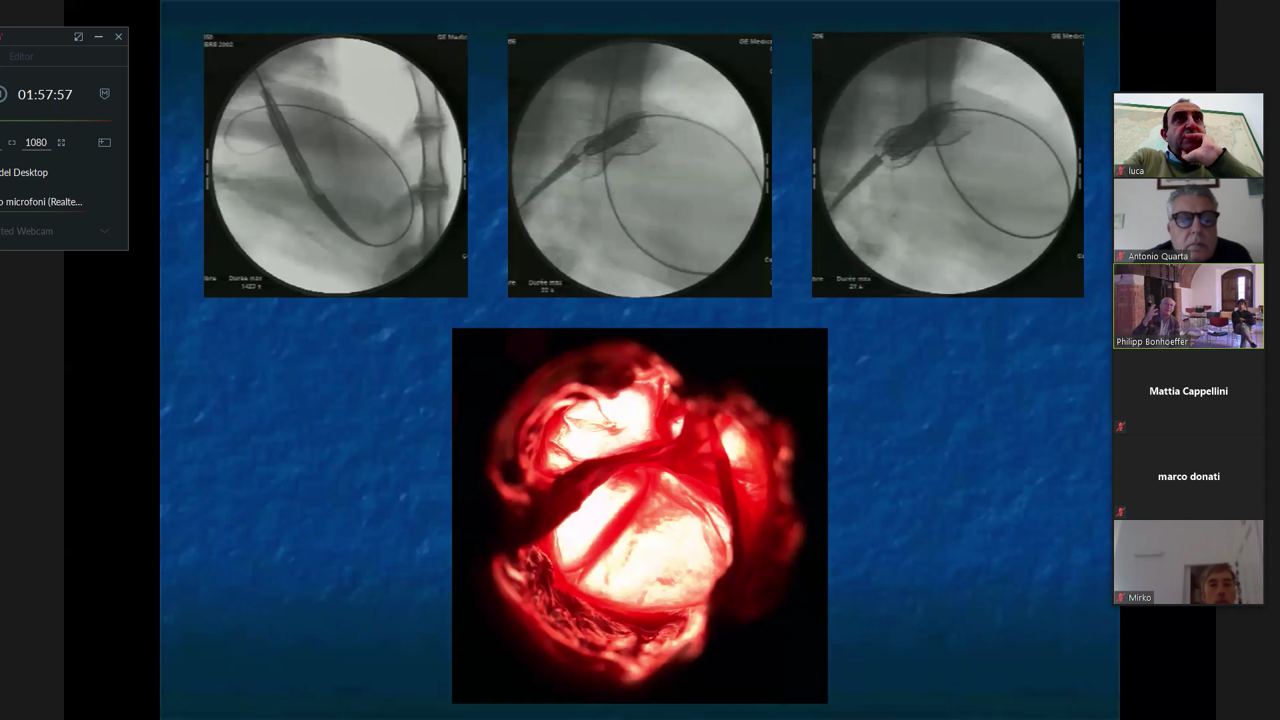

Negli anni mette a punto altre tecniche interventistiche tra le quali la rivoluzionaria procedura non invasiva che permette di inserire una valvola ricavata dalla giugulare bovina nell’arteria polmonare senza ricorrere all’intervento chirurgico a cuore aperto (valvola Melody).

La ricerca infatti non finisce mai, ed in collaborazione con una équipe multidisciplinare, composta da di cardiologi, radiologi, cardiochirurghi, ingegneri biomedici ed una ditta, ha sviluppato e progettato una seconda generazione di valvola che ha permesso di trattare un maggior numero di pazienti.